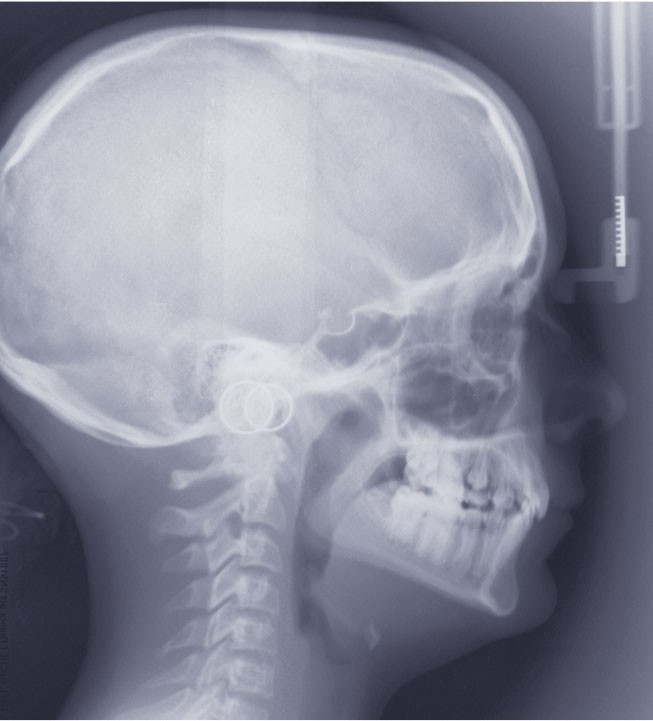

L’examen clinique exo-buccal révèle un visage équilibré en classe I squelettique tendance hypodivergente. De profil, le menton est marqué et le profil sous nasal très légèrement concave (fig. 1).